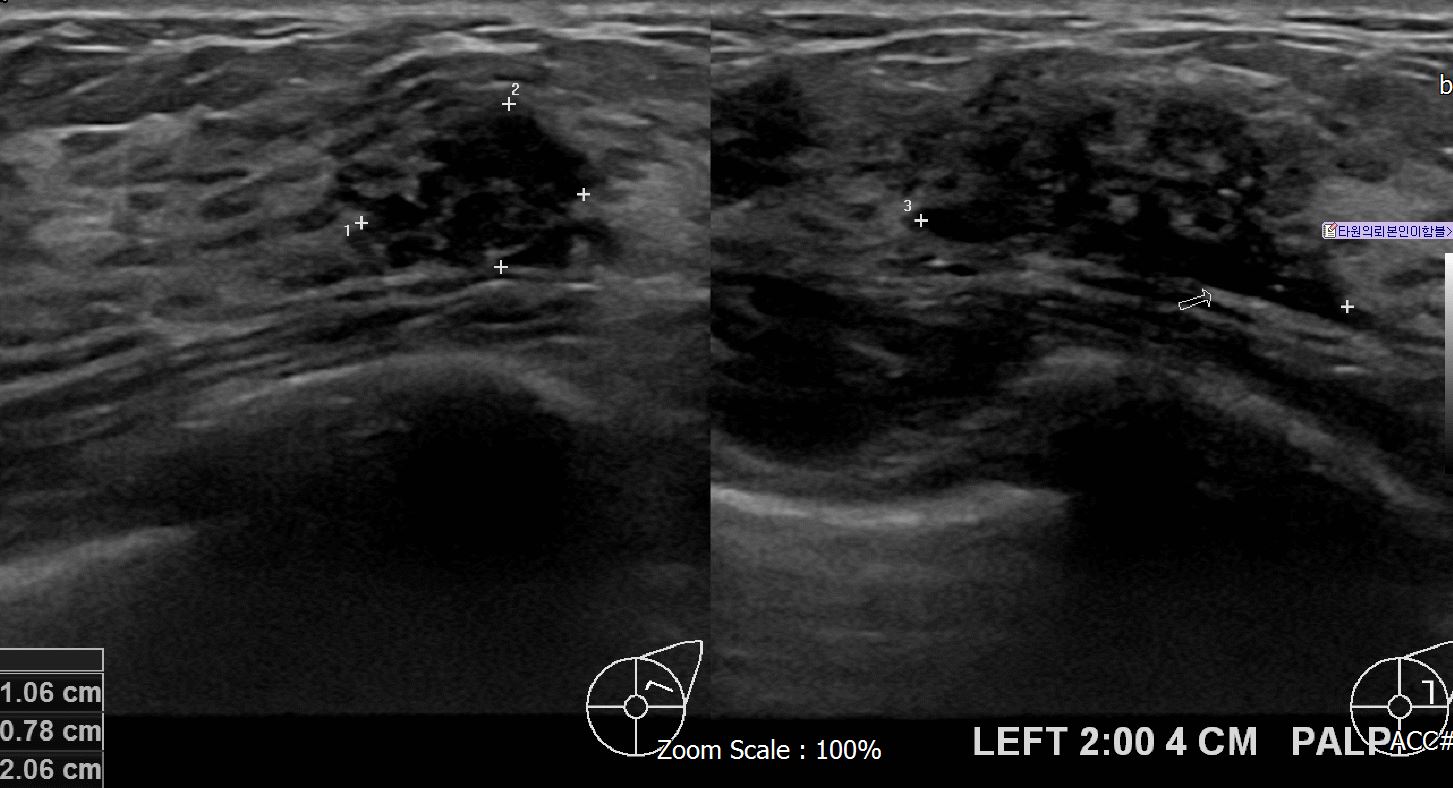

아산유외과 개원후 625번째 유방암 진단

상기 환자 본원에서 경과관찰중인 40대 여성으로 좌측에 의심스러운혹있어 조직검사 시행후 유방암 진단되었습니다.